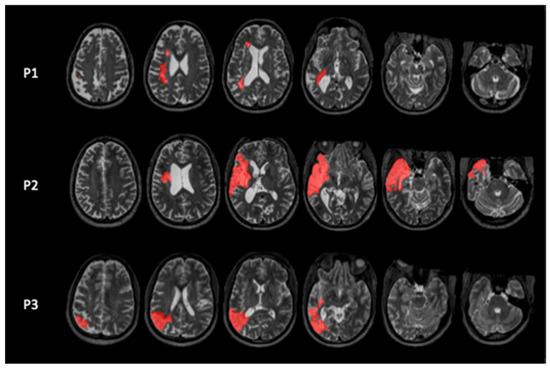

Background/Objectives: Repetitive Transcranial Magnetic Stimulation (rTMS) can enhance post-stroke aphasia recovery. The right Inferior Frontal Gyrus is the most common target in rTMS studies for inhibitory stimulation. However, lexicosemantic processes involve a large brain network including the Anterior Temporal Lobe (ATL). We hypothesize that rTMS targeting the ATL will improve lexicosemantic impairments in people with post-stroke aphasia. Methods: In a Single-Case Experimental Design, three people with post-stroke aphasia with lexicosemantic impairments performed Picture and Auditory Naming and Semantic Decision tasks five times a week for one or two weeks to establish baseline scores. Then, each participant received continuous inhibitory Theta Burst Stimulation targeting the right ATL, five times a week for two weeks. After each rTMS session, participants performed all linguistic tasks. A follow-up measurement was performed one month after the end of the study. Results: All participants showed significant improvement in the Picture Naming task, while only P1 improved in Auditory Naming accuracy. In the Semantic Decision task, only P2 showed improvement in both accuracy and RT, while P1 showed improvement in RT alone and P3 showed no improvement. Conclusions: The results suggest that ATL could be a potential target for future brain stimulation studies in aphasia involving lexicosemantic impairments. RTMS targeting the ATL may modulate the connected ventral semantic stream, leading to improvements in lexical access. This preliminary study highlights the possibility of selecting the cortical target for rTMS based on the clinical profile of the participant, an approach that will need further investigation in larger sham-controlled studies. Full article